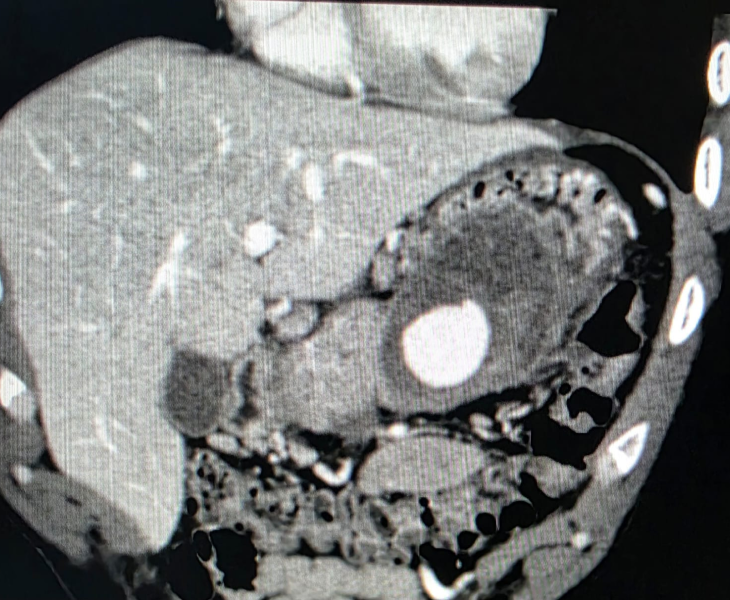

A pseudoaneurysm is a contained arterial bleed where blood escapes the artery through a tear and forms a sac outside the vessel wall. Unlike a true aneurysm, the sac is not made of normal artery wall, so it can rupture and cause severe internal bleeding.

Image‑guided embolization is a minimally invasive, life‑saving procedure that stops bleeding by blocking the injured artery from inside using coils or other embolic agents—often avoiding emergency surgery.

We use CT angiography and catheter angiography to identify the bleeding vessel precisely and then perform targeted embolization to seal it while preserving as much normal organ blood supply as possible.